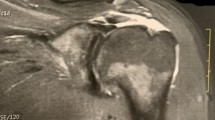

The MRI of shoulder were obtained preoperatively and 1 year postoperatively by 1.5-T MRI (Philips Medical System, Best, Netherlands). Both senior orthopedic surgeon (T.G. and B.P.) evaluated the preoperative and 1 year postoperative MRI scans. The size of the rotator cuff tear was classified by the Patte classification6 before time of surgery. In our study, 17 (40.5%) of the patients had stage 1 full thickness rotator cuff tears, 25 patients (59.5%) had stage 2 full thickness rotator cuff tears. The quality of the repair was evaluated as retear if identified as Sugaya type 4 and 5 (presence of a minor or major discontinuity) in the postoperative first year MRI7(Fig. 2).